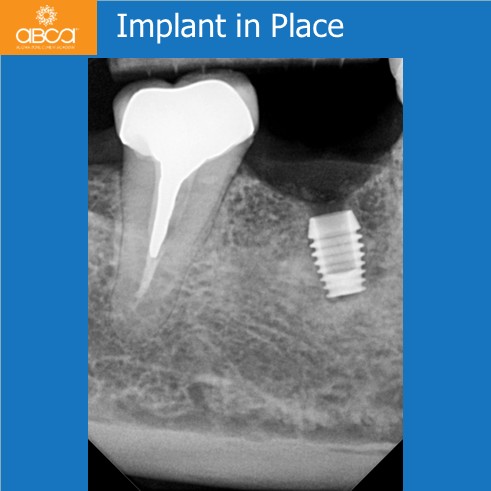

Treatment included extraction of tooth #46 (30) and debrided the site using Augma dedicated burs. We then filled the bone defect around the implant with 1 cc of Bond Apatite®.

The patient showed good healing and no clinical symptoms for up to five months after surgery. During the second procedure, we observed true bone regeneration, including reformation of the buccal cortical lamina. Histology (bone-particle sample) confirmed this finding. A Bicon implant (D 4.5 mm, L 6.0 mm) was placed with excellent primary stability and strong bleeding from the internal bone during osteotomy preparation.